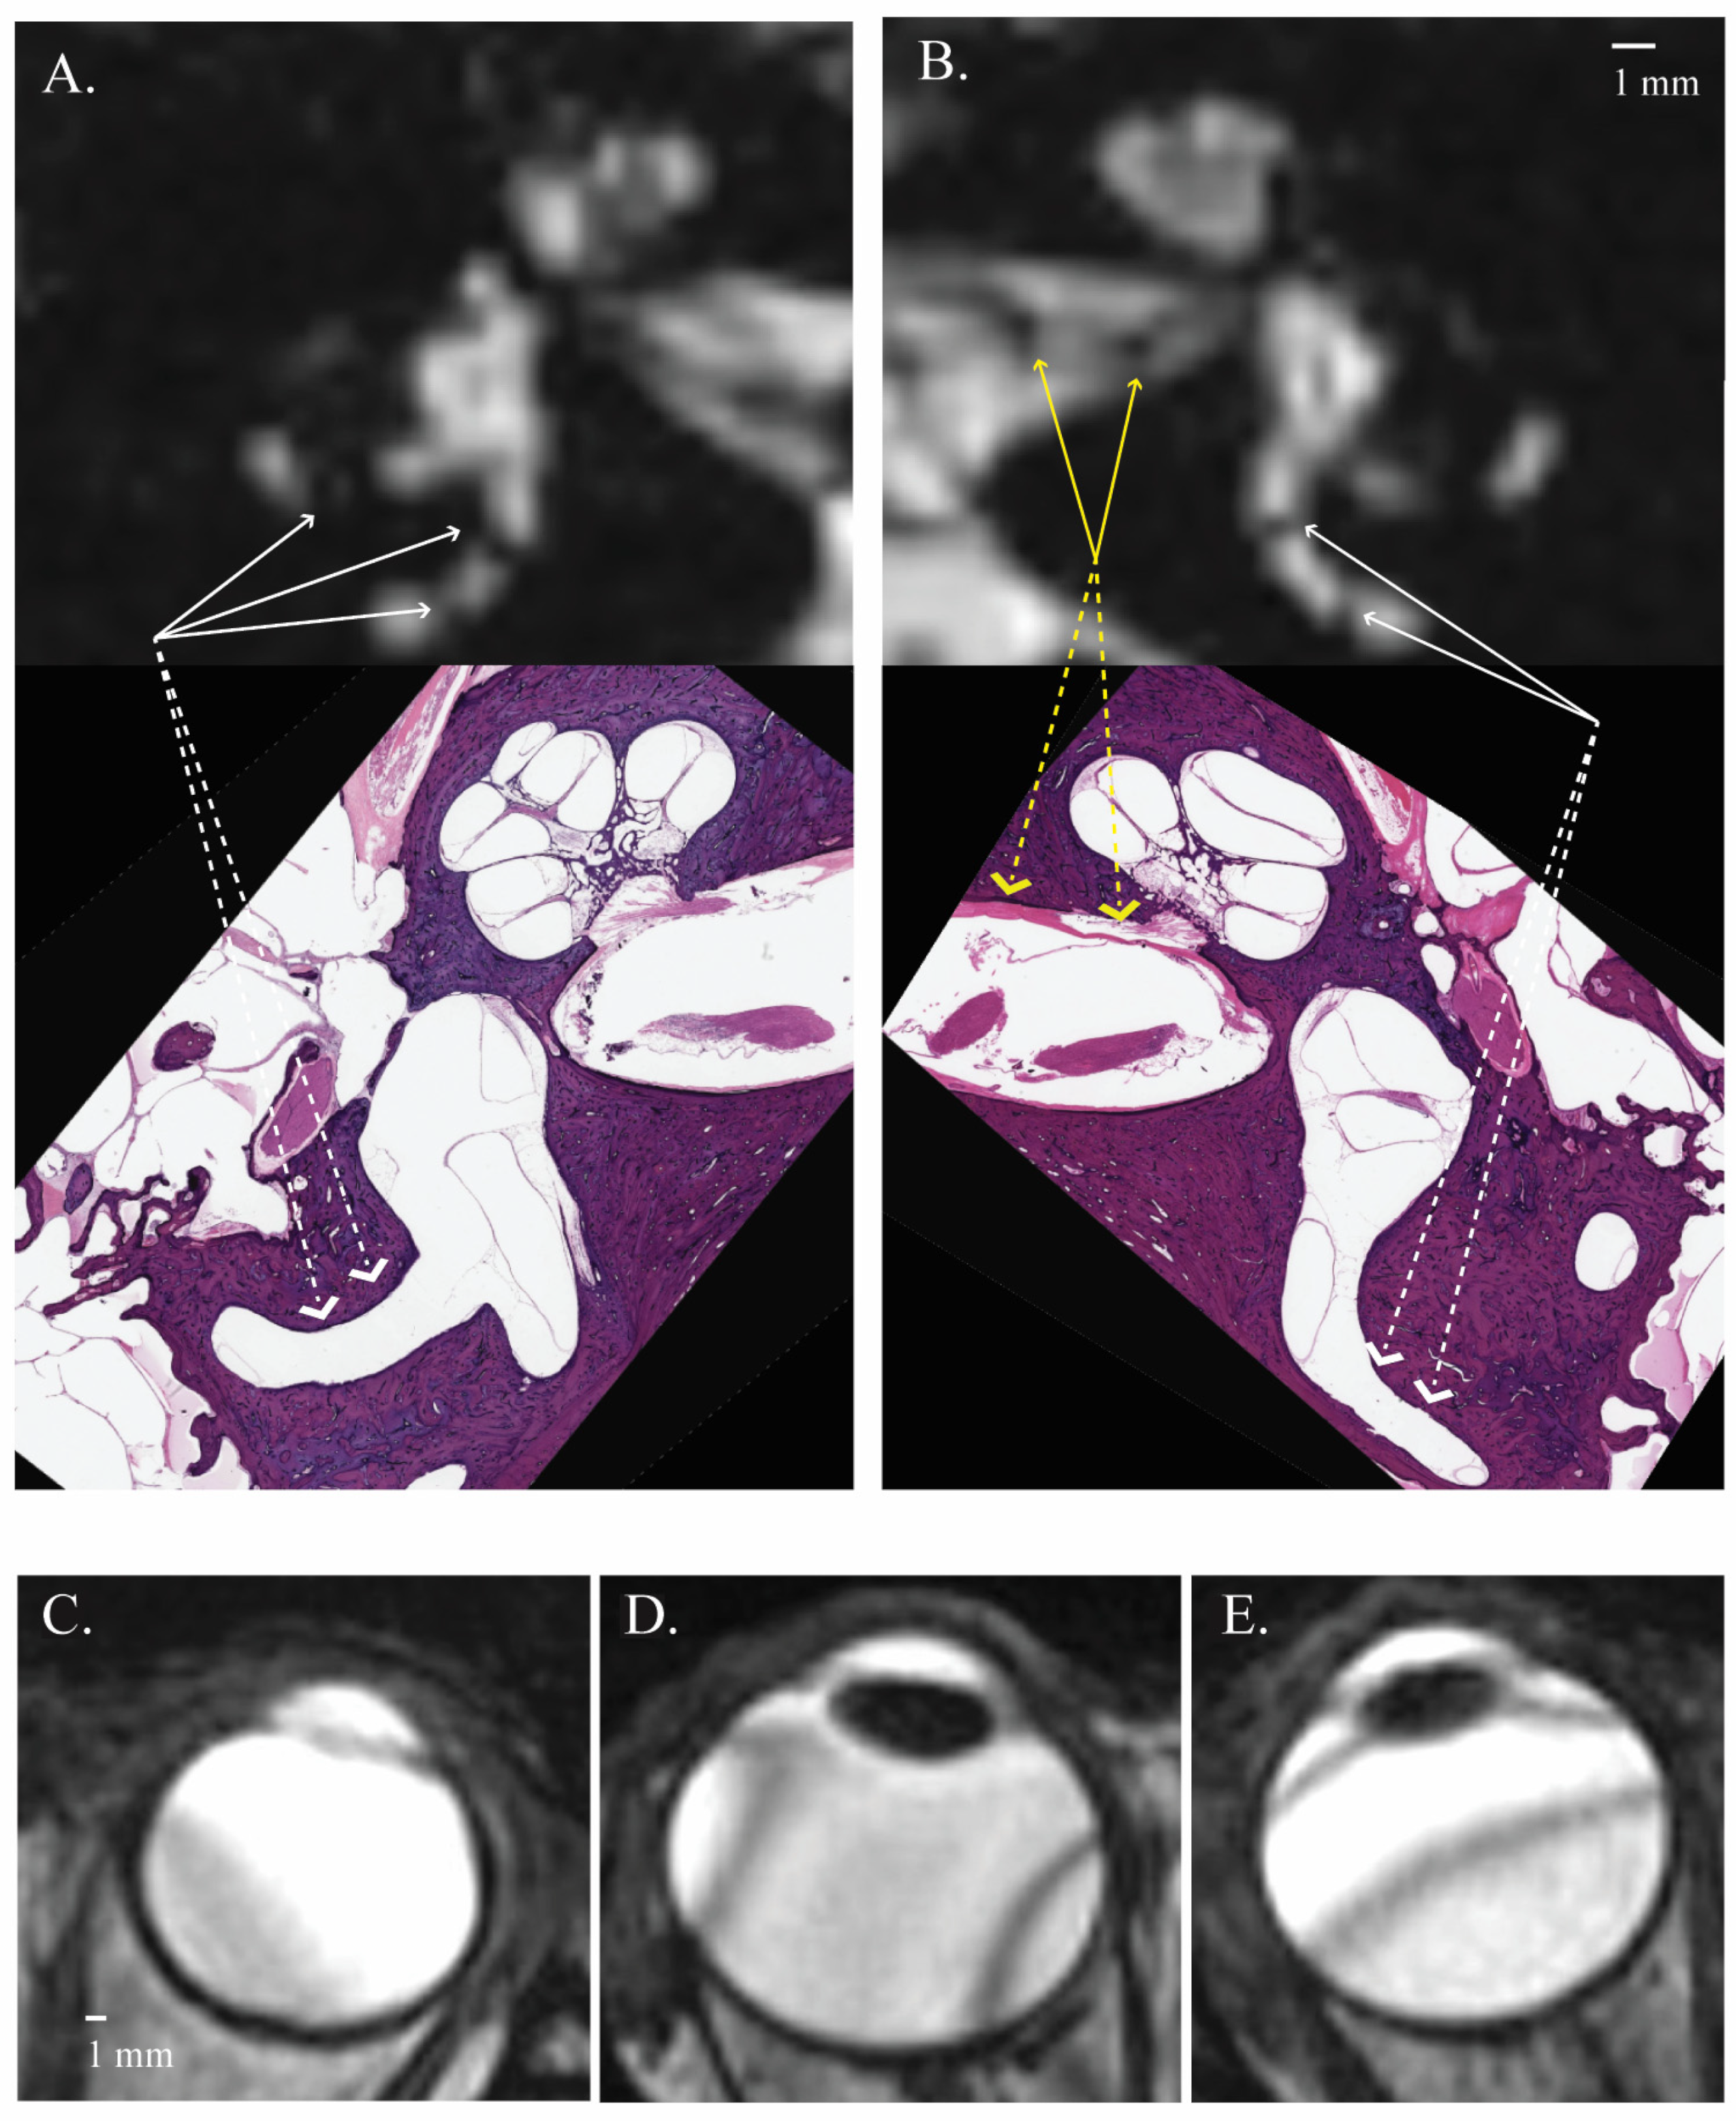

3.1. Signal Areas in the Inner Ear

- Ward, B.; Mair, A.; Nagururu, N.; Bauer, M.; Büki, B. Correlation between Histopathology and Signal Loss on Spin-Echo T2-Weighted MR Images of the Inner Ear: Distinguishing Artifacts from Anatomy. Am. J. Neuroradiol. 2022, 43, 1464–1469. [Google Scholar] [CrossRef] [PubMed]

- Cho, Y.S.; Kim, J.S.; Kim, M.B.; Koh, S.M.; Lee, C.H.; Kim, Y.-K.; Kim, H.-J.; Chung, W.-H. Validation of inner ear MRI in patients with Ménière’s disease by comparing endolymphatic hydrops from histopathologic specimens. Sci. Rep. 2021, 11, 17738. [Google Scholar] [CrossRef] [PubMed]